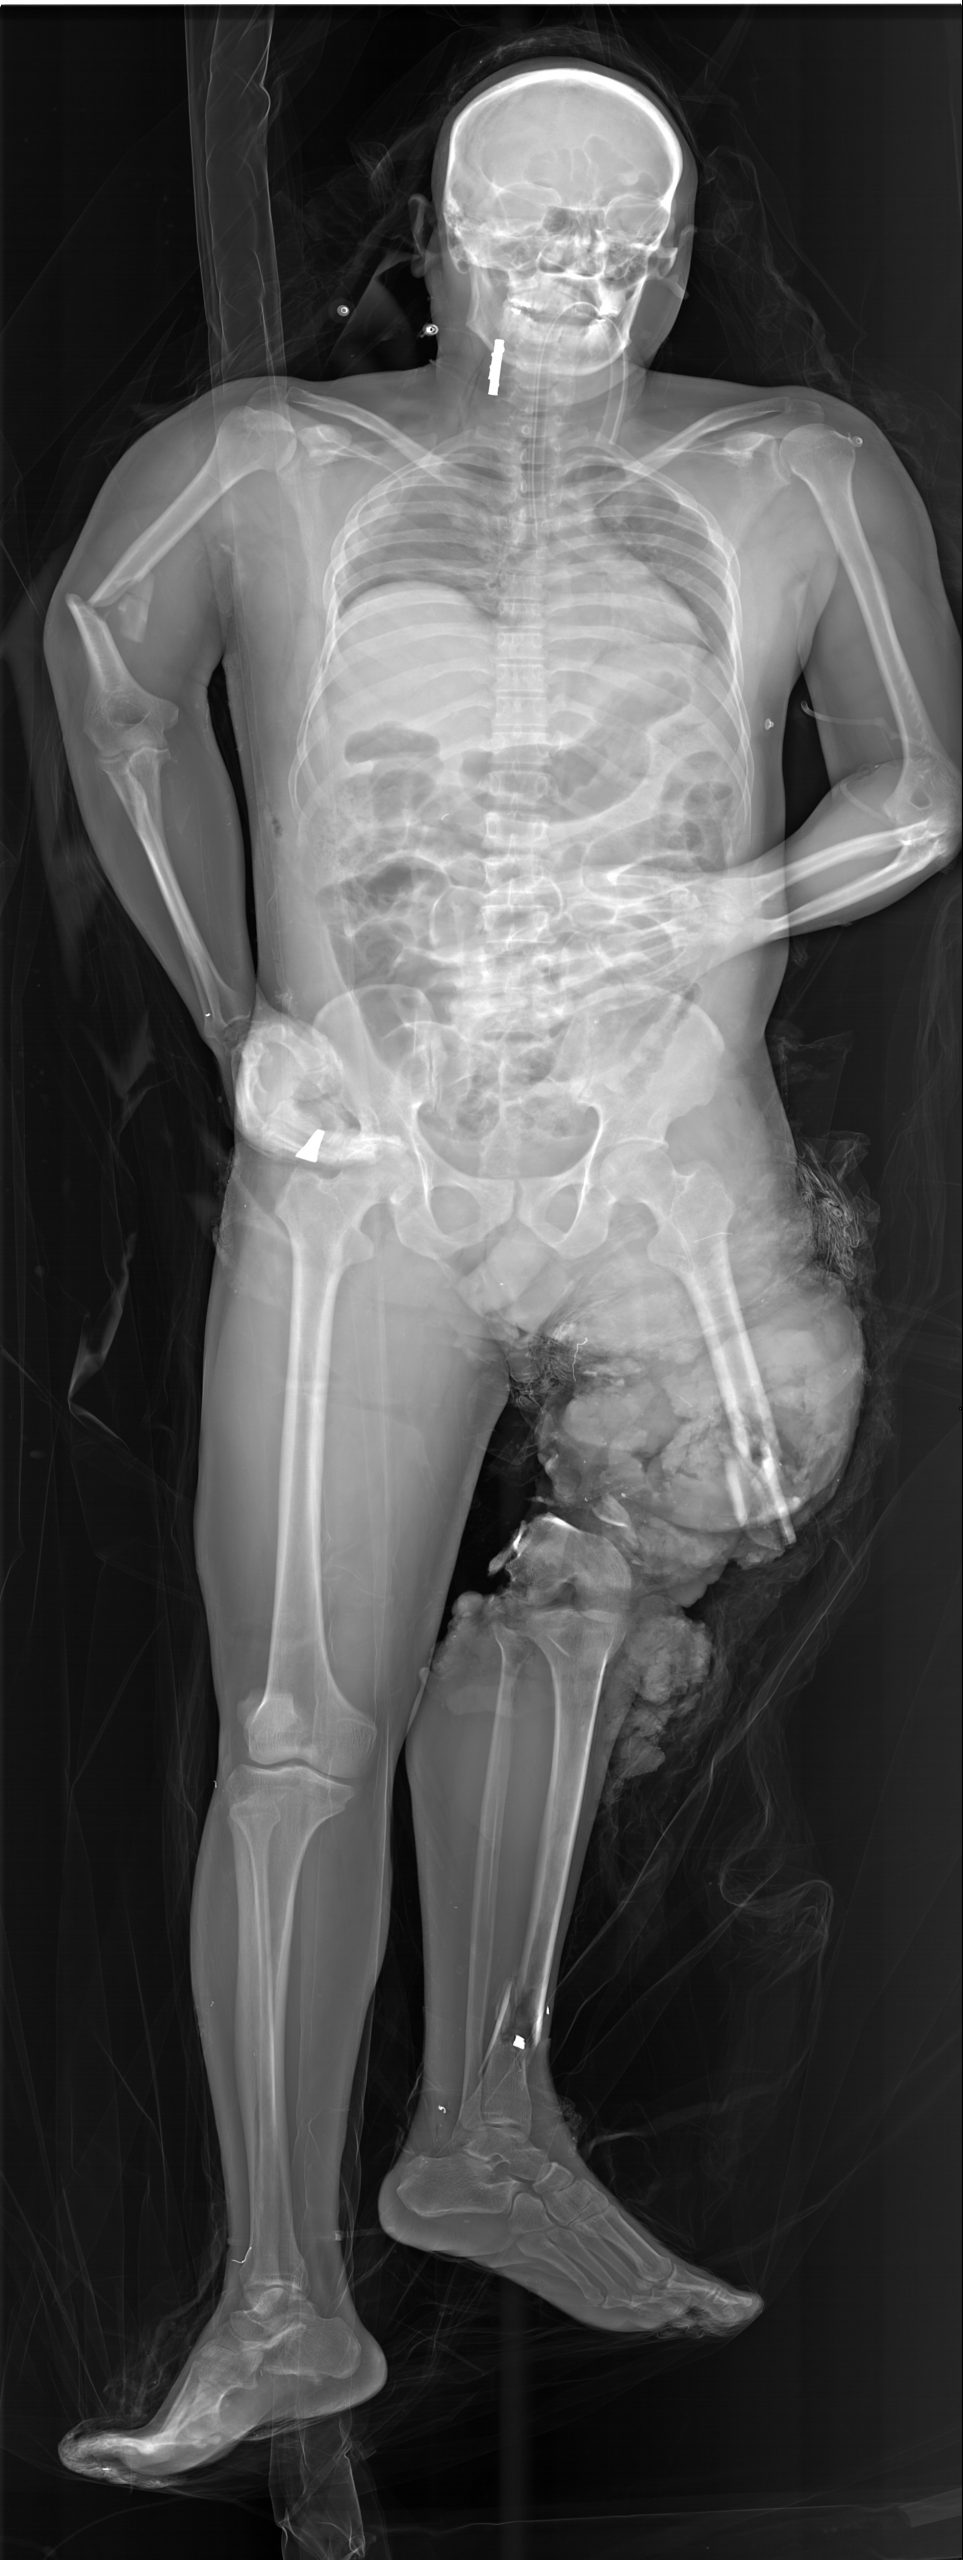

Klinik Görüntüler

Yukarıdaki örnek görüntüler, Lodox Xmplar-dr sisteminin her yaş ve vücut tipindeki hastalarda sunduğu yüksek çözünürlüklü tam vücut görüntüleme kapasitesini göstermektedir. Pediatrik hastalardan erişkinlere, düşük kilolu bireylerden yüksek vücut kitle indeksine sahip hastalara kadar geniş bir hasta grubunda net anatomik detay elde edilebilmektedir. Linear slot-scanning teknolojisi sayesinde kemik, yumuşak doku ve yabancı cisimler tek çekimde, ortalama 13–16 saniyede ve ultra düşük radyasyon dozu ile görüntülenir. Bu özellik, özellikle travma ve acil servis koşullarında hem hızlı tanı koymayı hem de radyasyona bağlı riskleri en aza indirmeyi mümkün kılar.